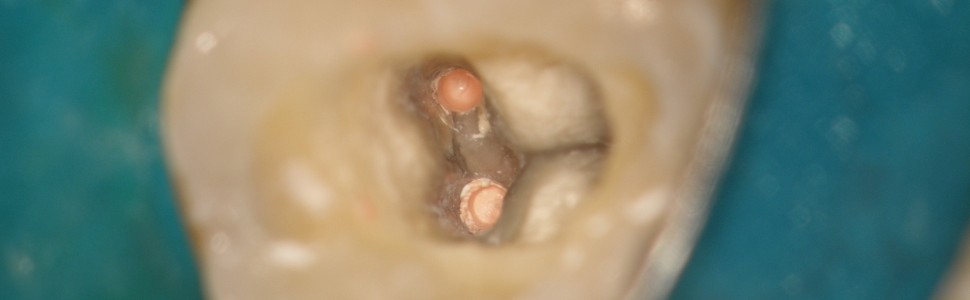

Ryc. 4. Obraz z mikroskopu zabiegowego (ząb 36). W kanale bliższym policzkowym widoczny fragment metalowego narzędzia.